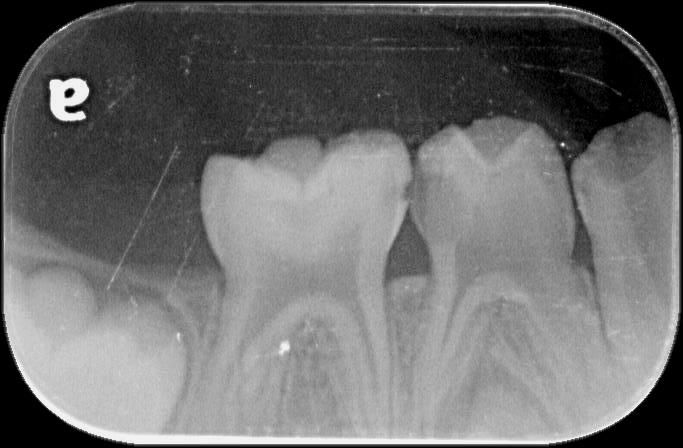

4살아이 눈으로도 시급한게 아래2개 위에 2개정도입니다.그런데 10개나 치료해야되고 8개를 크라운을 씌워야 된다고 하는데요 사진상에도 그런가요?

x-ray 사진상에서 치아와 치아 사이 충치가 있습니다. 어금니 치아와 치아 사이 충치는 눈에 잘 안보이지만 안으로 많이 진행된 경우가 많습니다.

2. 사진상에서 보이는 치아들은 충치가 있는게 다수이며 첫번째 사진의 오른쪽 치아, 세번째 사진의 왼쪽 치아는 충치가 심해보입니다.